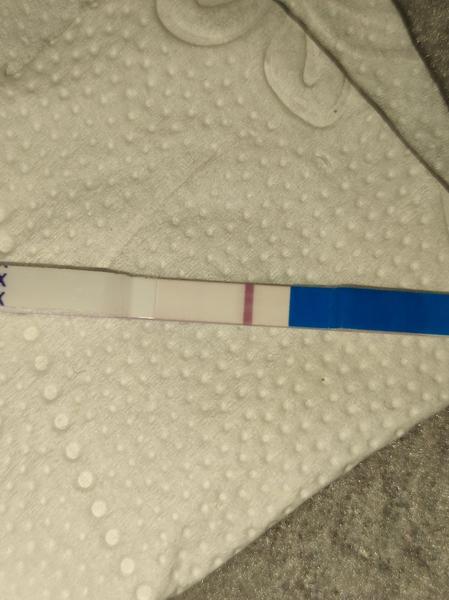

Duch na teste

ahojte babule, mam taku otazku...mate skusenost ze pocas 3 dni vam nesilnela druha ciarka na teste ale bola rovnaka???ako duch????

@zuzsat mne príde čiarka na teste @esmee3 jasná tiež.. a viditeľne sa postupne vyfarbuje. To už potom otázka testov a farby, a vylučovania hormónov, koncentrácii v mocu a tak. V porovnaní s tebou som zase mala veľmi nízke hcg.. a strašne pomaly to stúpalo, odmietla som hospitalizáciu lebo si mysleli všetci že to je mimoM tehotenstvo, teraz som v 23tt. Každý je v niečom iný..

@zuzsat baby uvidíme na sono ideme týždeň tak uvidíme. Len určite aj trvalo tomu vajíčku sa vôbec spojiť čiže reálne to mohlo byt až v nedeľu večer niekedy, a ja som testovala minulý pondelok a tam nebolo nič ani duch na 9dpo, prvý duch bol až v piatok, čo bolo 13dpo a to vtedy ukázal aj digi test poobede. Tak ja stále nestrácam nadej do utorka 😊je vidieť že tie testy sú raz tak silnejšie po tých 2dnoch, a možno už aj ten digi by ukázal 2-3t, v piatok bolo 1-2 neviem nemám doma iný test okrem týchto z dm

@zuzanaa2010 si zlata ale nechce sa mi verit .. kym nie je poriadne vidiet stale budem na pochybach

@esmee3 je to individuálne, mne pri prvom silnela oveľa pomalšie ako pri druhom 😎 nestresuj sa zbytočne testami. Niekto už á ducha 9 DPO a niekto až 13 DPO 😉